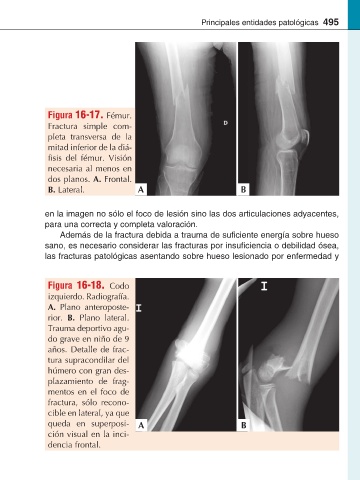

Figura 16-17. Fémur.

Fractura simple com-

pleta transversa de la

mitad inferior de la diá-

fémur. Visión

necesaria al menos en

dos planos. A. Frontal.

B. Lateral. A B

Figura 16-18. Codo

izquierdo. Radiografía.

A. Plano anteroposte-

rior. B. Plano lateral.

Trauma deportivo agu-

do grave en niño de 9

años. Detalle de frac-

tura supracondilar del

húmero con gran des-

plazamiento de frag-

mentos en el foco de

fractura, sólo recono-

cible en lateral, ya que

queda en superposi- A B

ción visual en la inci-

dencia frontal.